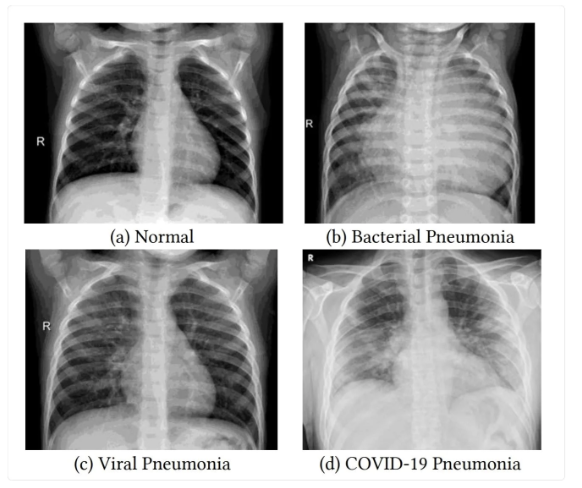

pnemonia (PNA)

lower resp infection that inflames the alveoli in one or both lungs

lots of causes (CAP, HAP, HCAP, VAP, ARF)

can be bacterial, viral, fungal